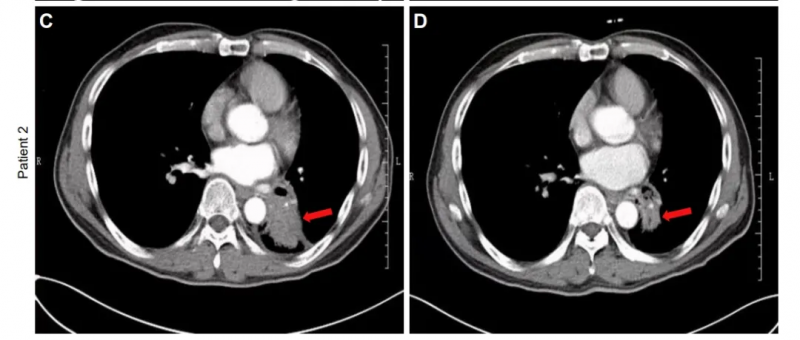

一项编号为NCT02843204的临床研究,评估了帕博利珠单抗(PD-1抑制剂)联合NK细胞治疗晚期NSCLC的安全性与有效性。研究纳入109例既往治疗失败、PD-L1表达阳性(TPS≥1%)的患者,分为联合治疗组和单药组。

结果突出:

- 客观缓解率(ORR)提升明显:联合组ORR为36.4%,显著高于单药组的18.5%;

- 中位总生存期(OS)延长2.2个月(15.5个月 vs 13.3个月),且多疗程NK输注患者OS达18.5个月;

- 中位无进展生存(PFS)达6.5个月,优于对照组的4.3个月。

典型病例中,一位68岁女性患者治疗90天后,肺内肿瘤明显缩小;另一例57岁男性患者同样达到部分缓解(PR),肿块显著缩小。

图片来源:JCI,版权归原作者所有

这一方案被誉为晚期肺癌的“黄金组合”,不仅提高客观缓解率,还显著延长患者生存,是免疫联合治疗的重要方向。